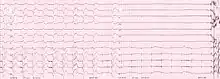

Biventricular pacing

Cardiac resynchronization therapy (CRT) is used for people with heart failure in whom the left and right ventricles do not contract simultaneously (ventricular dyssynchrony), which occurs in approximately 25–50% of heart failure patients. To achieve CRT, a biventricular pacemaker (BVP) is used, which can pace both the septal and lateral walls of the left ventricle. By pacing both sides of the left ventricle, the pacemaker can resynchronize the ventricular contractions.

CRT devices have at least two leads, one passing through the vena cava and the right atrium into the right ventricle to stimulate the septum, and another passing through the vena cava and the right atrium and inserted through the coronary sinus to pace the epicardial wall of the left ventricle. Often, for patients in normal sinus rhythm, there is also a lead in the right atrium to facilitate synchrony with the atrial contraction. Thus, the timing between the atrial and ventricular contractions, as well as between the septal and lateral walls of the left ventricle can be adjusted to achieve optimal cardiac function.

CRT devices have been shown to reduce mortality and improve quality of life in patients with heart failure symptoms; a LV ejection fraction less than or equal to 35% and QRS duration on EKG of 120 ms or greater.[18][19]

Biventricular pacing alone is referred to as CRT-P (for pacing). For selected patients at risk of arrhythmias, CRT can be combined with an implantable cardioverter-defibrillator (ICD): such devices, known as CRT-D (for defibrillation), also provide effective protection against life-threatening arrhythmias.[20]